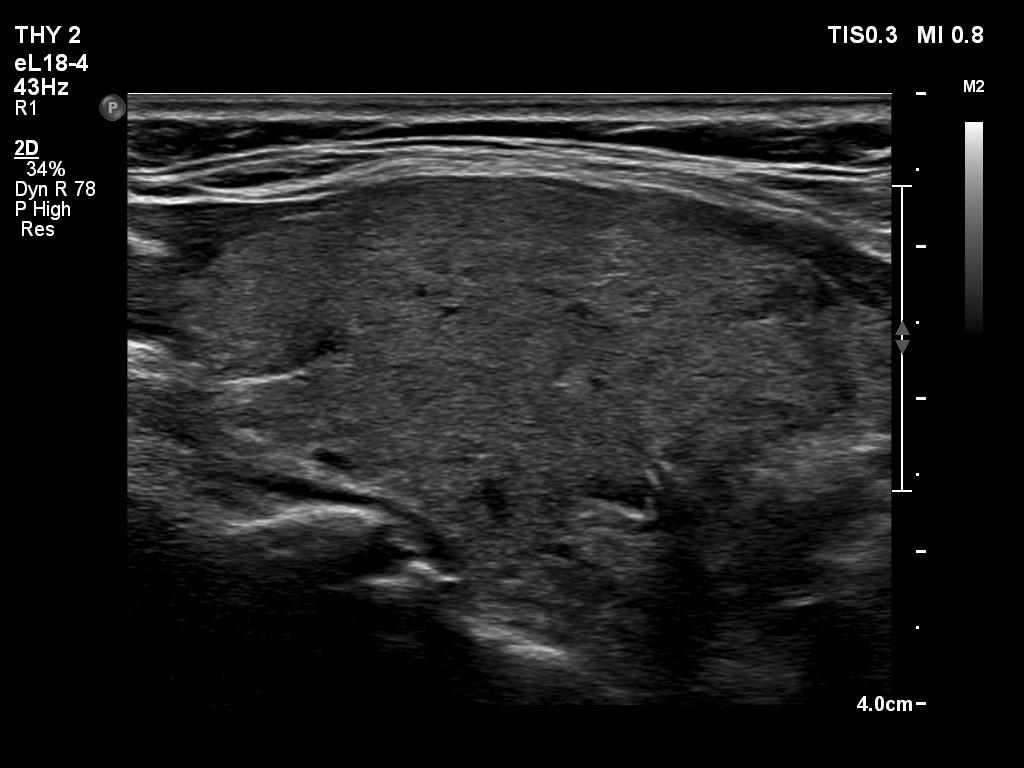

Right lobe, longitudinal scan

Right lobe, longitudinal scan. None of the discrete lesions has clinical significance.